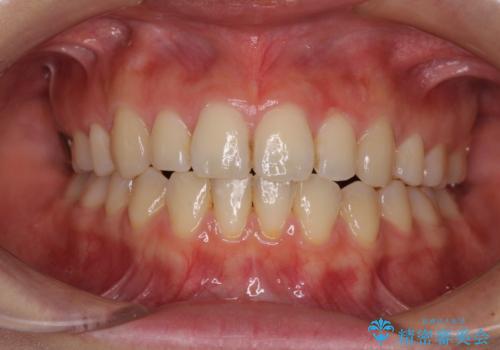

上顎の狭窄歯列 インビザラインによる拡大矯正

- 前歯の叢生と臼歯のクロスバイトを気にして来院された患者様です。

急速拡大装置による上顎の側方拡大を行い、その後はインビザラインより歯列を改善することとしました。

20代後半以降の男性は上顎骨の側方拡大処置の成功率が低く、今回も骨を拡大することができませんでした。

しかしながら、歯列を側方に拡大することができ、その後はインビザラインにて叢生を解消することができました。